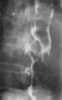

Superficial spreading carcinoma of esophagus

Esophageal cancer is cancer arising from the esophagus—the food pipe that runs between the throat and the stomach. Symptoms often include difficulty in swallowing and weight loss. [Source: Wikipedia ]